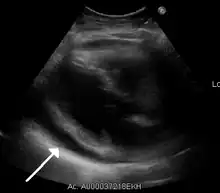

A pericardial effusion due to pericarditis

Echocardiogram (ultrasound): when pericardial effusion is suspected, echocardiography usually confirms the diagnosis and allows assessment of the size, location and signs of hemodynamic instability.[4] A transthoracic echocardiogram (TTE) is usually sufficient to evaluate pericardial effusion and it may also help distinguish pericardial effusion from pleural effusion and MI. Most pericardial effusions appear as an anechoic area (black or without an echo) between the visceral and the parietal membrane.[1] Complex or malignant effusions are more heterogeneous in appearance, meaning they may have variations in echo on ultrasound.[5] TTE can also differentiate pericardial effusion based on the size. Although it's difficult to define size classifications because they vary with institutions, most commonly they are as follows: small <10, moderate 10–20, large >20.[5] An echocardiogram is urgently needed for evaluation when there is concern for hemodynamic compromise, a rapidly developing effusion or history of recent cardiac surgery/procedures.[1]